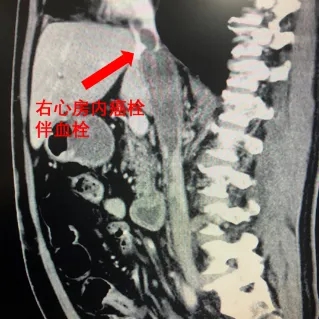

北医三院完成疑难手术:肿瘤从左肾爬进心脏

——【医学界】9月1日,讲述泌尿外科张树栋团队与心脏外科等多科合作,成功救治肿瘤从左肾爬进心脏的15CM癌栓患者。一根长达15cm的癌栓,从左肾肿瘤处沿着下腔静脉延伸至胸腔,直逼患者心脏……近日,“医学界”从北京大学第三医院(以下简称“北医三院”)处获悉,该院泌尿外科成功为一位患者实施高难度手术,完整取出了癌栓。北医三院泌尿外科主任、学科带头人张树栋告诉“医学界”,患者王先生此前被诊断为肾癌伴下腔静脉癌栓,癌栓已从肾静脉侵入下腔静脉,...